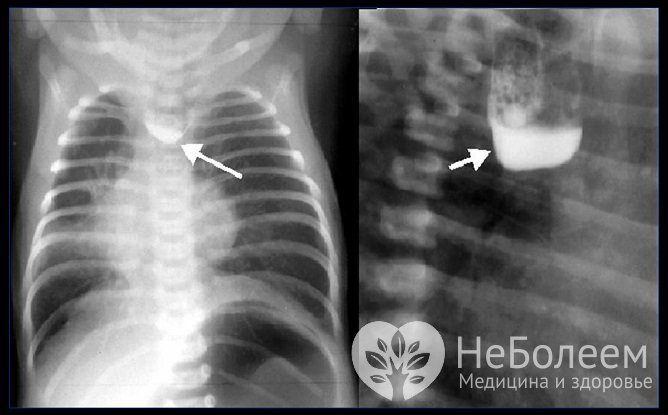

Рентгеновский снимок атрезии пищевода у ребенка

Рентгеновский снимок атрезии пищевода у ребенкаАтрезия пищевода требует дифференциальной диагностики со следующими патологиями:

Для установления вида атрезии пищевода выполняют бронхоскопию и эзофагоскопию. Рентгенография с контрастированием бариевой взвесью при данной патологии нередко сопровождается развитием респираторных осложнений, способных стать причиной смерти младенца, поэтому такое исследование выполняют крайне редко и только по строгим показаниям.